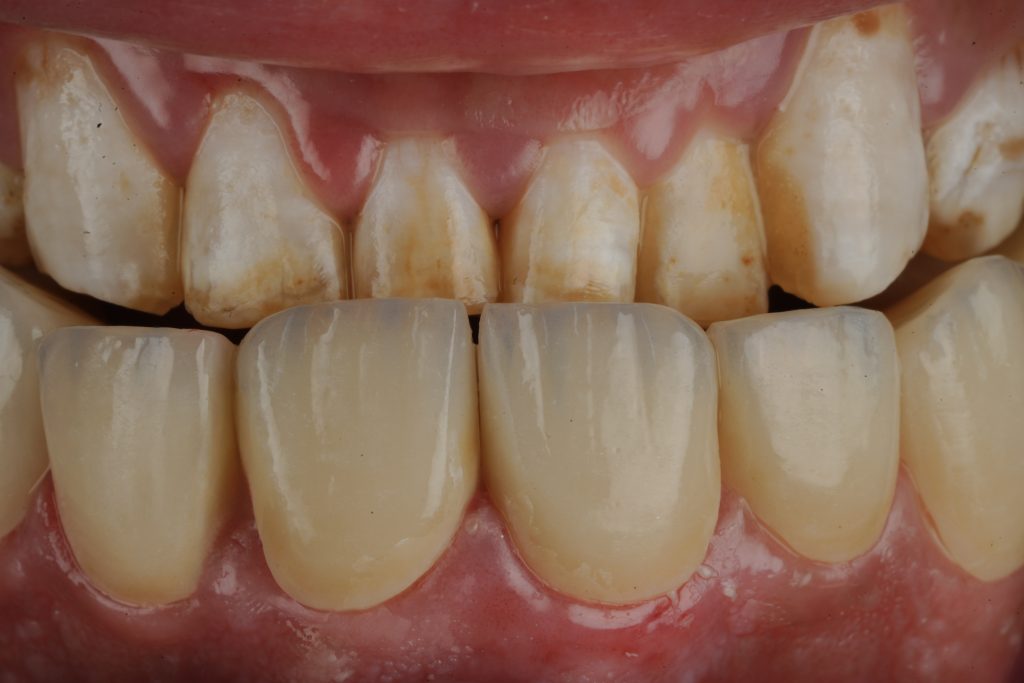

The patient sought esthetic improvement for uneven incisal edges, discolored anterior teeth, and disproportionate gingival display (Fig 1). A digital smile simulation and mock-up try-in were performed to assess tooth proportion, midline alignment, and incisal curvature. The plan prioritized enamel conservation and optical harmony.